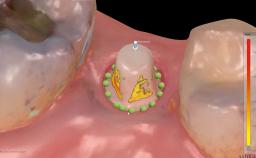

Immediate Replacement of Four Mandibular Anterior Teeth with a Conventionally Loaded Implant-Supported Fixed Dental Prosthesis

This case from German Gallucci, Adam Hamilton, and Teresa Chanting Sun details immediate placement with a conventional loading protocol (type 1C). It demonstrates a digital workflow combined with risk assessment to determine the best possible treatment approach for replacing mandibular anterior teeth.

| Timing of placement | Immediate Placement (extraction sockets) (Type I) |

| Available apical bone to achieve primary stability | Sufficient height ( ≥ 4 mm) and width (> 2 mm around apex of planned implant) |

| Socket walls | Intact |

| Thickness of buccal wall | 2mm or greater |

| Anticipated residual defect after implant placement | 2 mm or less |